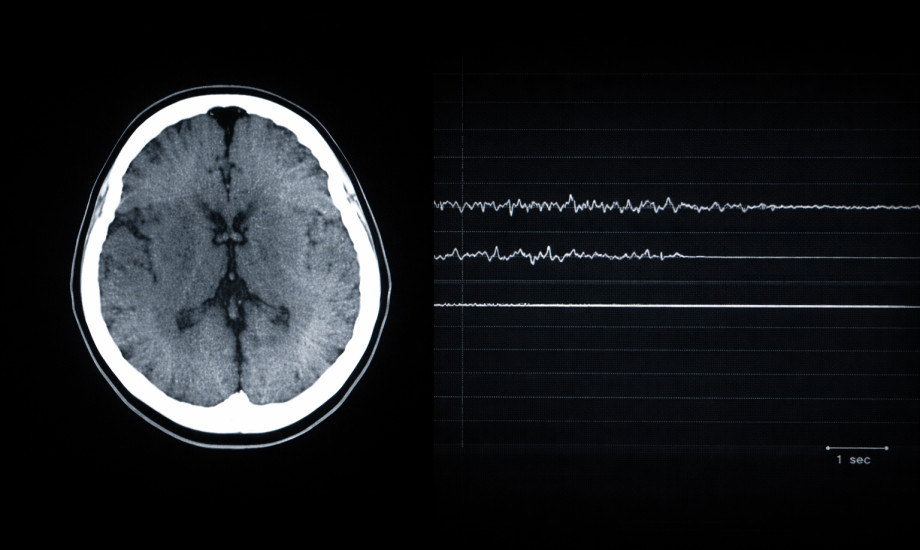

Eine 21-Jährige stellt sich mit akuter neurologischer Symptomatik vor. Seit acht Jahren lebt sie mit einem systemischen Lupus erythematodes mit artikulären, kutanen, renalen und hämatologischen Manifestationen sowie einer Hypothyreose. In den vergangenen vier Monaten setzte sie eigenständig ihre gesamte Medikation ab.